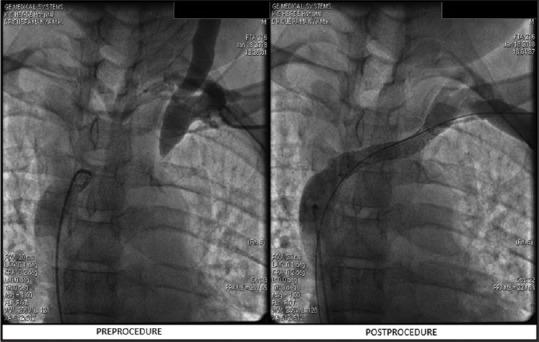

Central venous stenosis (CVS) refers to a significant stenosis of a large intrathoracic vein, such as the subclavian, brachiocephalic, or the superior vena cava (hemodialysis, HD). Percutaneous transluminal angioplasty (PTA) with or without stent placement has been the recommended as the preferred approach to CVS. A total of 10 consecutive HD patients with documented CVS over a 2-year time period from April 2017-April 2019 underwent percutaneous angioplasty and stent insertions under sedation. The procedure was performed by the interventional cardiologist in the institute. One patient underwent only PTA, whereas nine (90%) had PTA with primary stent insertion. Primary patency was 90% at 3 months, 80% at 6 months while at 12 months, it was 70% and remained at 70% at 24 months. We did not find any association between age, gender, diabetic status, dialysis vintage, or previous catheter infection with procedural patency. Central venous stenosis can be treated successfully with percutaneous angioplasty and primary stenting. Despite advances, prevention of CVS should be the primary approach.

摘要

中心静脉狭窄(CVS)是指胸腔内大静脉,如锁骨下静脉、头臂静脉或上腔静脉(血液透析,HD)的严重狭窄。经皮腔内血管成形术(PTA)无论是否置入支架,都已被推荐为治疗CVS的首选方法。在2017年4月至2019年4月的两年时间里,共有10例连续的有记录的HD患者患有CVS,在镇静状态下接受了经皮血管成形术和支架置入术。该手术由该机构的介入心脏病专家进行。1例患者仅接受了PTA,而9例(90%)接受了PTA并同时置入了初级支架。3个月时的初级通畅率为90%,6个月时为80%,12个月时为70%,24个月时仍为70%。我们没有发现年龄、性别、糖尿病状态、透析时间或既往导管感染与手术通畅率之间存在任何关联。经皮血管成形术和初级支架置入术可以成功治疗中心静脉狭窄。尽管有进展,但预防CVS仍应是主要方法。